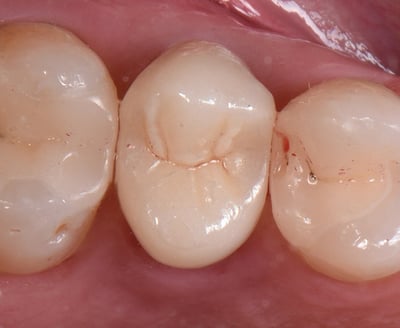

Eindresultaat na cementeren. |

Zowel directe als indirecte, posterior restauraties kunnenuitdagend zijn, vanwege de hoeveelheid beschikbare materialen waaruit de behandelaar moet kiezen. De jonge patiënt in deze klinische casus had een losgekomen kroon op de tweede, bovenste pre-molaar en twee kapotte restauratiesop de eerste molaar en pre[1]molaar. Bij een meervoudige restauratie zoals deze moet een indirecte benadering worden overwogen. In dit geval is gekozen voor partiële, adhesieve restauraties van lithiumdisilicaat en een volzirkonium kroon. Verschillende materialen met verschillende indicaties, maar met gebruik van slechts één cement.

3M™ RelyX™ Universal Composietcement

3M™ Scotchbond™ Universal Plus Adhesief